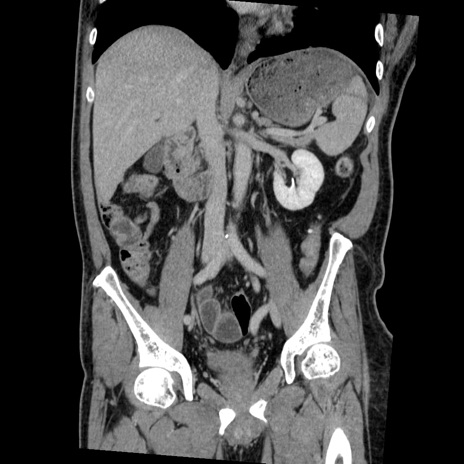

症例22(冠状断像)

【症例】50歳代男性

【主訴】腹痛

【現病歴】AVMからの被殻出血のため回復期リハ病棟入院中。 本日午後3時頃急に下腹部痛が出現した。

【既往歴】AVM、被殻出血、虫垂炎、高血圧

【身体所見】意識晴明、左半身不全麻痺、会話の理解は良好、36.5°C、腹部:膨隆、全体に板状硬、下腹部正中に圧痛点あり、反跳痛-、筋性防御不明、右下腹部にope scar

【データ】WBC 9400、CRP 0.06

横断像